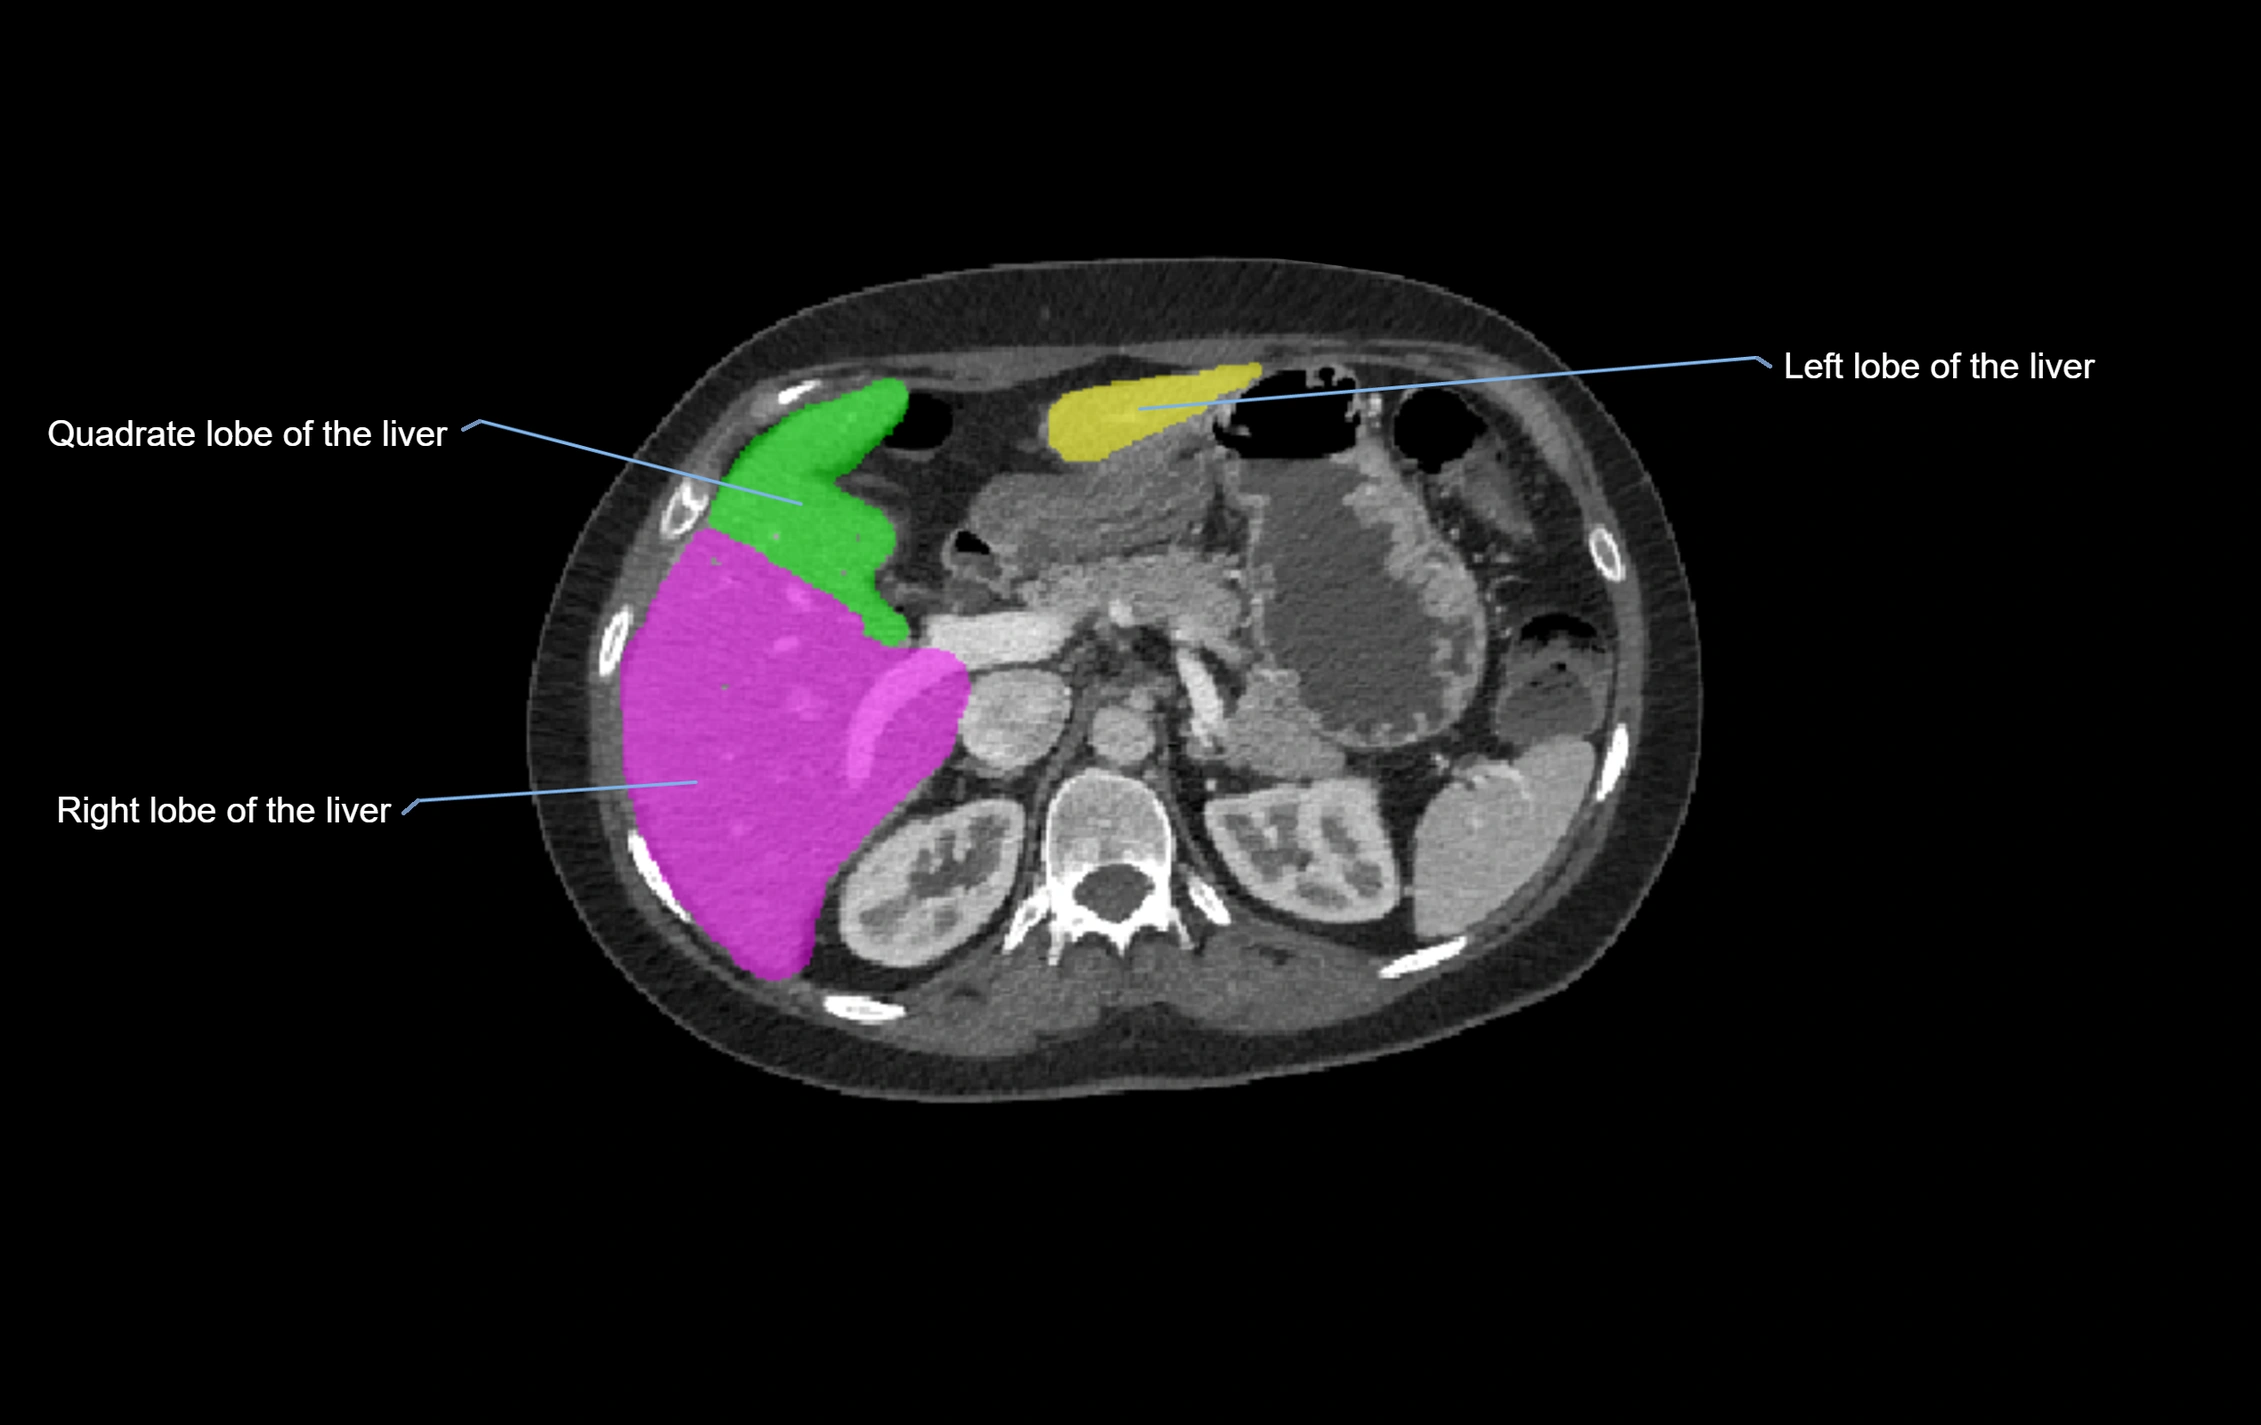

The caudate lobe of the liver is a distinct anatomical subdivision of the liver, designated as segment I in Couinaud’s classification. It lies on the posterior surface of the liver, between the fissure for the ligamentum venosum (left boundary) and the groove for the inferior vena cava (IVC) (right boundary). Superiorly, it is related to the posterior liver surface, and inferiorly it is separated from the left lobe by the porta hepatis.

The caudate lobe is unique because it receives dual portal venous and arterial inflow from both the right and left portal veins and hepatic arteries. It also has independent venous drainage directly into the IVC via multiple small hepatic veins, unlike other lobes that drain through the three main hepatic veins.

MRI image

image